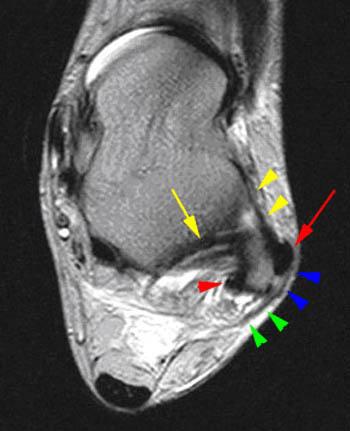

Tears of the peroneus brevis tendon are more frequent than reported in the literature. It is possible to have peroneus brevis muscle pain, peroneus brevis tendon pain, or peroneus brevis insertional pain into the fifth metatarsal. Physical signs such as swelling along the course of the peroneal tendon sheath, pain with ever … The peroneus longus also everts the sole of the foot, and from the oblique direction of the tendon across the sole of the foot is an important agent in the maintenance of the transverse arch. Fused peroneus brevis and longus is a much rarer abnormality, in which there is no separation between the two lateral leg muscles. If you suffer a torn tendon, you will need surgery to repair it. The peroneus brevis tendon attaches the peroneus brevis muscle to the fibula, or lower leg bone, at one end and to the bottom of the fifth metatarsal at the base of the little toe. Because of the vague pain associated with structures of the lateral ankle, peroneal tears are frequently misdiagnosed. The peroneus brevis (also known as fibularis brevis) is a short muscle that lies at the lateral part of the lower leg deep to the peroneus longus. It is one of the three peroneus muscles (pernoeus longus, peroneus brevis and peroneus tertius). Apply ice or cold therapy as soon as possible after injury. The peroneus brevis anatomy consists of the peroneus brevis muscle, the peroneus brevis tendon, and the peroneus brevis insertion into the base and styloid process of the fifth metatarsal. Though it's usually asymptomatic, it can contribute to tendonitis of the peroneus brevis tendon.

Fused peroneus brevis and longus is a much rarer abnormality, in which there is no separation between the two lateral leg muscles. The peroneus brevis (also known as fibularis brevis) is a short muscle that lies at the lateral part of the lower leg deep to the peroneus longus. The peroneus longus and brevis muscles plantarflex the foot, in conjunction with the tibialis posterior, antagonizing the tibialis anterior and peroneus tertius, which are dorsiflexors of the foot. They commonly occur at the level of the retromalleolar groove. Though it's usually asymptomatic, it can contribute to tendonitis of the peroneus brevis tendon.

Ice can be applied for 10 minutes every hour and reduce the. Epidemiology small published case series include. The peroneus brevis anatomy consists of the peroneus brevis muscle, the peroneus brevis tendon, and the peroneus brevis insertion into the base and styloid process of the fifth metatarsal. Tears of the peroneus brevis tendon are more frequent than reported in the literature. 01.05.2021 · peroneus brevis tendon tears are acute or chronic, and may be asymptomatic or associated with lateral ankle pain and/or instability. Fused peroneus brevis and longus is a much rarer abnormality, in which there is no separation between the two lateral leg muscles. Physical signs such as swelling along the course of the peroneal tendon sheath, pain with ever … The peroneus brevis tendon attaches the peroneus brevis muscle to the fibula, or lower leg bone, at one end and to the bottom of the fifth metatarsal at the base of the little toe. Apply ice or cold therapy as soon as possible after injury. Aktueller nomenklatur sollte peroneus durch fibularis ersetzt werden, s. Because of the vague pain associated with structures of the lateral ankle, peroneal tears are frequently misdiagnosed. The peroneus brevis (also known as fibularis brevis) is a short muscle that lies at the lateral part of the lower leg deep to the peroneus longus. The peroneus longus also everts the sole of the foot, and from the oblique direction of the tendon across the sole of the foot is an important agent in the maintenance of the transverse arch.